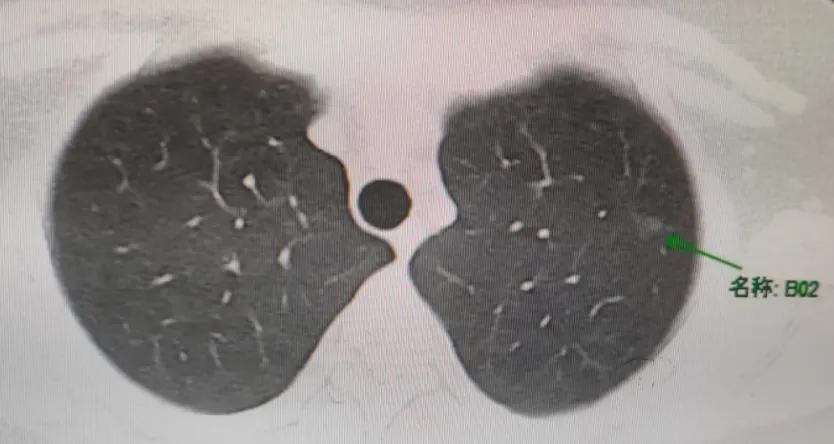

今天的这位也是这样,一个23岁,还在享受人生最好时光的小姑娘,因为长时间咳嗽就诊,查出双肺多发磨玻璃结节,最大的一个结节是9mm×6mm。小姑娘非常棒,不乱于心,不畏将来。自己已经茫然无措了,还可以很坚强的安慰着父母,然后独自面对所有压力。

很快,小姑娘顺利的完成了手术。术后病理,3个微浸润肺腺癌,一网打尽,手术即治愈。

来返图了,星期一面诊,因为太紧张,一片空白,手足无措!又担心影响主任看后面的患者,所以很多话还没来得及说,借贴吧来表达一下感谢啦。过程很艰辛,发现结节以后哭也哭过,闹也闹过,埋怨过为什么会是我。遇到主任以后,我有了主心骨有了信念。9月27面诊,主任开了入院,10月19日手术,切掉右肺所有高危结节(一网打尽!!!),3个微浸润,和术前诊断一模一样。判断准才能给患者更好的建议与治疗,主任真的太厉害啦!星期一术后三月复查,目前一切安好,现在左肺听主任的话半年随访。